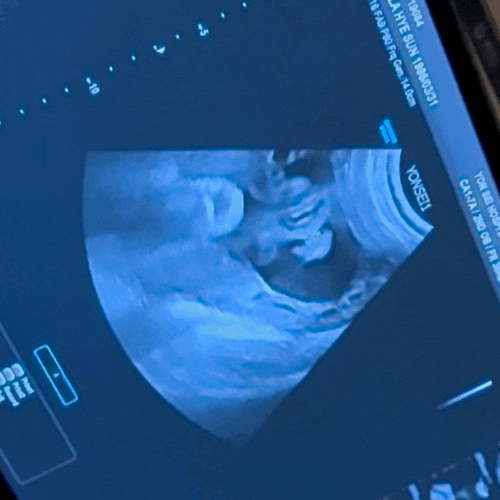

임신 35~38주 기록 - 막달 증상, 신촌 세브란스 36/ 37주 검진, 자궁근종

주수별 증상 기록 35주 : · 코막힘과 코마름 증상, 숨쉴때 답답하다. (원래 임신전엔 없던 증상인데, 찾아...